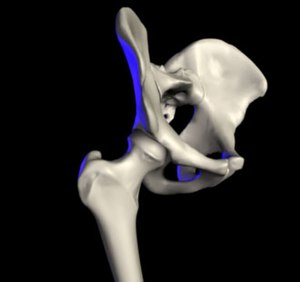

Das Hüftgelenk (lat. Articulatio coxae) ist nach dem Kniegelenk das zweitgrößte Gelenk der Säugetiere. Der Oberschenkelknochen (Femur) und das Becken (Pelvis) bilden dabei die knöchernen Gelenkpartner. Es ist vor allem bei den (menschlichen) Fortbewegungsarten des Gehens, bei dem es im Gegensatz zum Laufen keine Flugphase gibt, eingebunden.

Der Oberschenkelknochen bildet am oberen Ende einen großen kugelförmigen Kopf (Caput femoris). Dieser stellt eine relativ regelmäßig gekrümmte Zwei-Drittel-Kugel mit einem Radius von durchschnittlich 2,5 Zentimetern dar. Lediglich der gelenknahe (proximale) Pol formt eine plane Fläche um die Einziehung des Oberschenkelknochenkopfes (Fovea capitis femoris), um die zu übertragende Last von einem Punkt auf einen Ring zu verschieben. Der Oberschenkelknochenkopf ist durchgehend von hyalinem Knorpel überzogen, weist in seinen Hauptbelastungszonen jedoch eine besonders ausgeprägte Schicht von etwa 2,5 bis 3,5 Millimetern auf. Zum Oberschenkelknochenhals (Collum femoris) hin nimmt die Dicke sukzessiv ab.

Am Aufbau des Gegenstückes, der Hüftgelenkpfanne (Acetabulum), sind alle drei Beckenknochen beteiligt: Das Dach wird vom Darmbein (Os ilium) gebildet, das Schambein (Os pubis) begrenzt vorne (ventral) und das Sitzbein (Os ischii) hinten-unten (dorsokaudal) den Rand des Beckens mit seiner Vertiefung, das so genannte Acetabulum („Essignäpfchen“).

Stellt man sich die Pfanne als hohle Halbkugel vor, beträgt ihr Radius beim Menschen je nach Körpergröße etwa 2,7 Zentimeter. Eine bogenförmige Faserknorpellippe (Labrum acetabuli bzw. Limbus acetabuli) geht jedoch stellenweise über den Äquator der Halbkugel hinaus und umgreift regelrecht den Oberschenkelknochenkopf. Daher spricht man beim Hüftgelenk auch von einem Nussgelenk (Sonderform des Kugelgelenkes). Zum Schambeinloch (Foramen obturatum) ausstrahlend ist die Pfannenlippe hingegen unterbrochen (Incisura acetabuli), sodass sie eine halbmondförmige Gestalt annimmt. Dieser unterbrochene Teil der Pfanne wird von einem Querband (Ligamentum transversum acetabuli) überbrückt.

Umhüllt wird das Hüftgelenk von der kräftigsten Gelenkkapsel des menschlichen Körpers, der straffen Hüftgelenkskapsel (Capsula articularis coxae). Sie wird über innerhalb der Kapsel gelegene Bänder stabilisiert und in der Mitte vom Ringband umgurtet.

Die äußere Schicht der Gelenkkapsel (Membrana fibrosa capsulae) entspringt am Limbus acetabuli und überdeckt trichterförmig fast vollständig den Oberschenkelknochenhals, um vorne an der Linie zwischen den beiden Oberschenkelrollhügeln (Linea intertrochanterica) zu inserieren. Hinten (dorsal) ist die Ansatzlinie etwa fingerbreit oberhalb des Randes (Crista intertrochanterica) zwischen den Oberschenkelknorren (Trochanter major und Trochanter minor) entfernt.